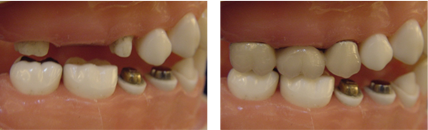

缺牙導致牙齒移位 - 臨床實例一

缺牙導致牙齒移位 - 臨床實例二

上面的牙往下墜,下面的牙往上長,前面的牙往外飆 – 咬合崩塌牙周病,蛀牙;這些現象必然發生,時間越久,問題越大,而且除非藉由矯正及其他牙科治療,無法修正。